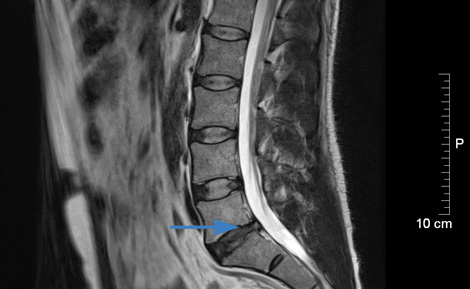

Bild vorher: Massenvorfall mit Nervenwurzelkompression

Bild 6 Monate nach Behandlung: Bandscheibenvorfall komplett zurückverlagert, Nervenwurzel nicht behindert

Patient, 39 Jahre, Bandscheibenvorfall Lendenwirbelsäule L5/S1, massive Beschwerden mit Lähmungserscheinungen, auswärts Operationsindikation gestellt, Patient wünscht konservative Therapie

Patient : völlig beschwerdefrei, komplette Ausheilung.